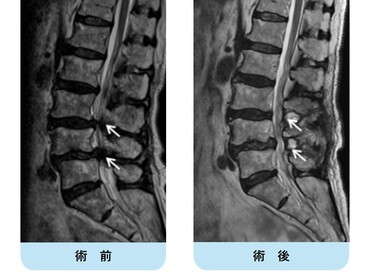

術前MRIでは腰椎椎間板ヘルニアを認め、神経の圧迫を認めています。後方からのヘルニア摘出術により神経症状は劇的に改善しました。

術前MRIでは脊柱管の狭窄を認め、神経の圧迫を認めています。後方からの除圧術後、神経への圧迫は改善しています。